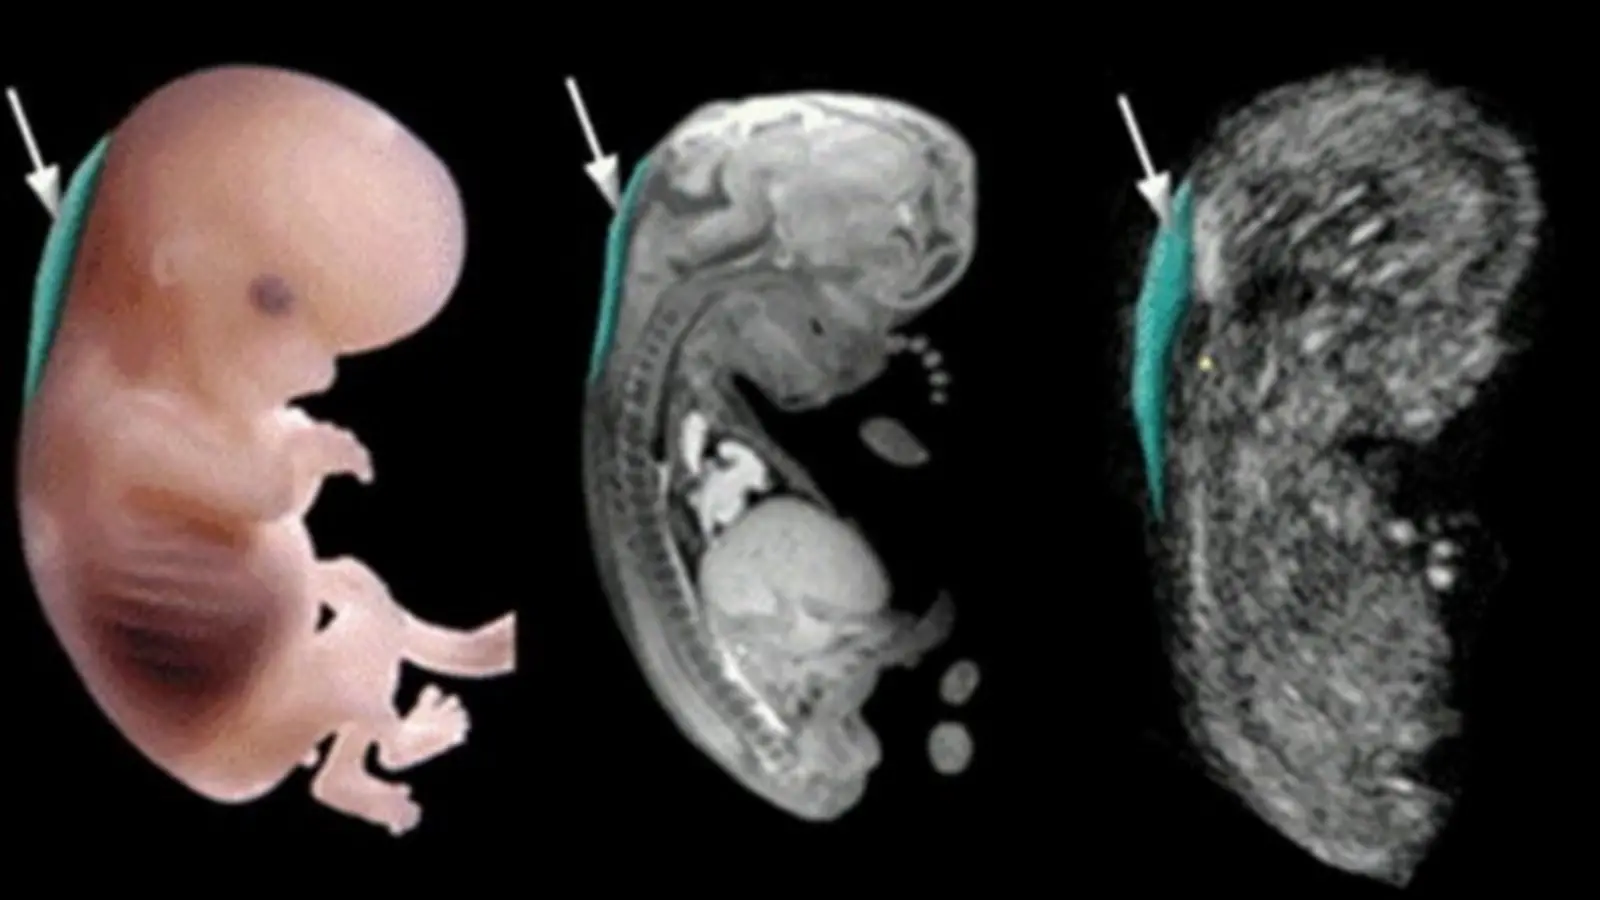

Độ mờ da gáy là chỉ số đo sự tích tụ chất dịch ở vùng da sau gáy của thai nhi

Đo độ mờ da gáy được thực hiện từ 11 tuần 6 ngày đến 13 tuần 6 ngày